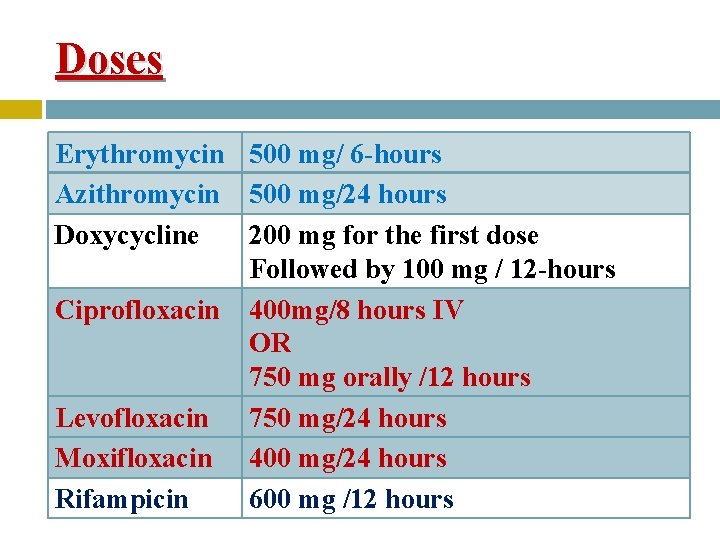

Doses Erythromycin 500 mg/ 6 -hours Azithromycin 500 mg/24 hours Doxycycline 200 mg for the first dose Followed by 100 mg / 12 -hours Ciprofloxacin 400 mg/8 hours IV OR 750 mg orally /12 hours Levofloxacin 750 mg/24 hours Moxifloxacin 400 mg/24 hours Rifampicin 600 mg /12 hours